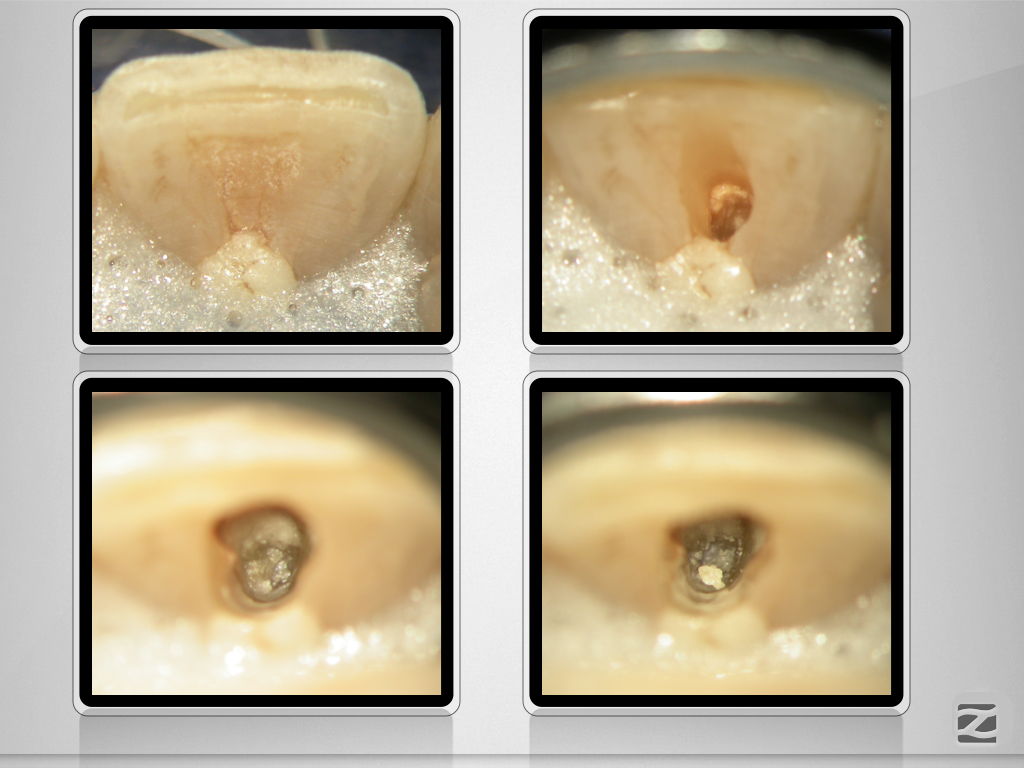

11D.004

Unverhofft und nicht oft.